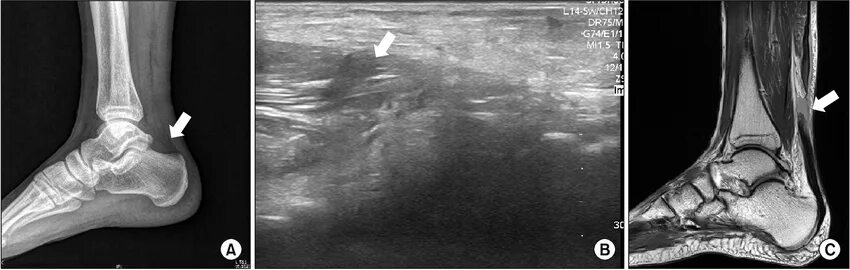

Мрт ахиллового сухожилия